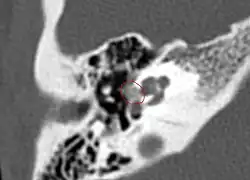

Otosclerosis on CT can be graded using the grading system suggested by Symons and Fanning.[21]

• Grade 1, solely fenestral;

• Grade 2, patchy localized cochlear disease (with or without fenestral involvement) to either the basal cochlear turn (grade 2A), or the middle/apical turns (grade 2B), or both the basal turn and the middle/apical turns (grade 2C); and

• CT scan of otosclerotic focus in the anterior footplate

Grade 3, diffuse confluent cochlear involvement (with or without fenestral involvement).